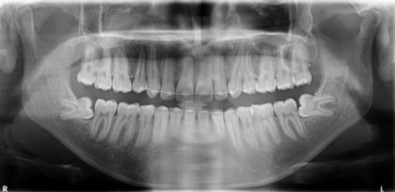

Cephalometric analysis revealed a skeletal Class II pattern, with an orthognathic maxilla and retrognathic mandible with high mandibular plane angle and severely proclined maxillary and mandibular incisors with increased lower anterior facial height. (Figure 3).